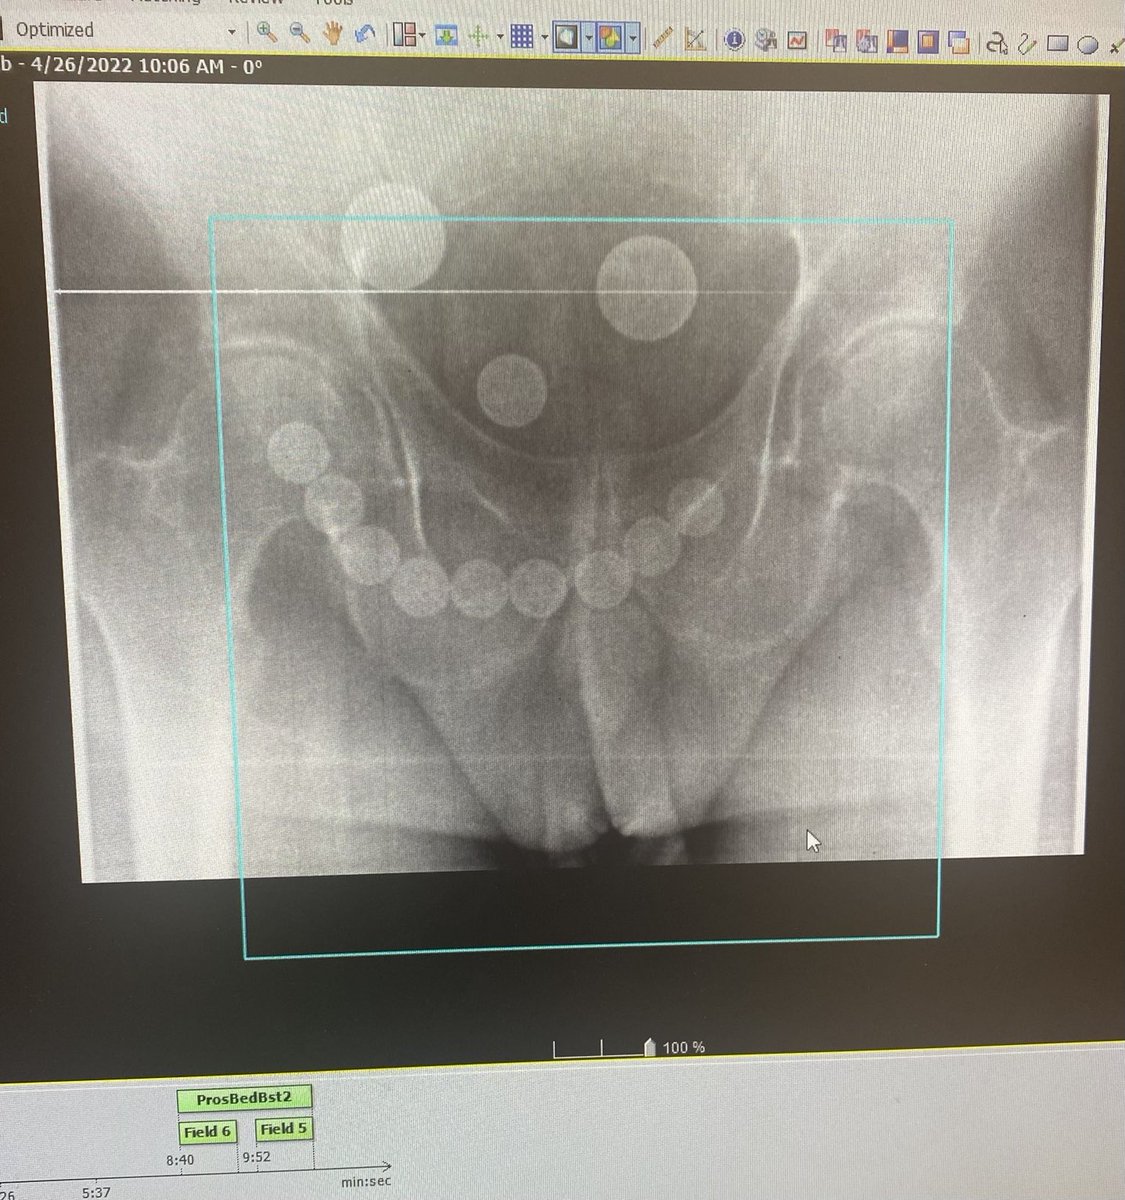

Excited to hit the #gym 4 some #cognitive resilience/reserve training following a very mentally stimulating work week. Below is recent example of the mental intensity/neural activation required which may b sustained when faced w other “life demands”. Come join me and learn more